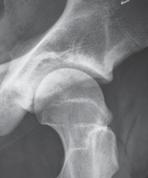

Fråga 2012-14 3p

50 årig man som två år tidigare opererats

med en ocementerad protes. Han blev aldrig smärtfri efter operationen. Söker på grund av lårsmärtor som förvärras vid belastning. Daglig hög analgetikakonsumtion. CRP 7 (normalvärde <5). Använder 1 kryckkäpp.

a. Vilken diagnos bör du misstänka i första hand? (1p)

b. Motivera ditt svar och ange förslag till behandling. (2p)

a. Patienten har smärtor både i vila och vid belastning. CRP är antytt förhöjd. Protesen har en bred zon proximalt. Det föreligger en breddökad kortex och uttalade periostala pålagringar.

Mycket talar för en djup och lågvirulent infektion. (1 p). (Stammen är sannolikt lös även om man inte kan se någon säker sjunkning. Cupen sitter troligen fast eftersom man inte ser någon zon)

b. Man bör göra en ledpunktion och odla helst vid två efterföljande tillfällen (1p). Härefter protesbyte (1p). Om agens inte är känt bör revision utföras i två seanser.